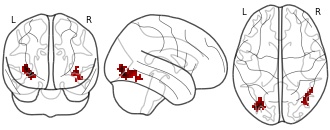

"name": "VBM_HeterogeneityMap",

"description": "Abnormal gray matter in BPD. Brain regions with significant heterogeneity (i.e. between-study variance) in the comparison of patients with BPD and healthy controls. Results are thresholded at at p<.005 & k>20. Note: Results are based on meta-analysis of group comparisons. Note2: Results were updated (see Erratum for this publication)",

"add_date": "2016-01-21T18:23:32.131003+01:00",